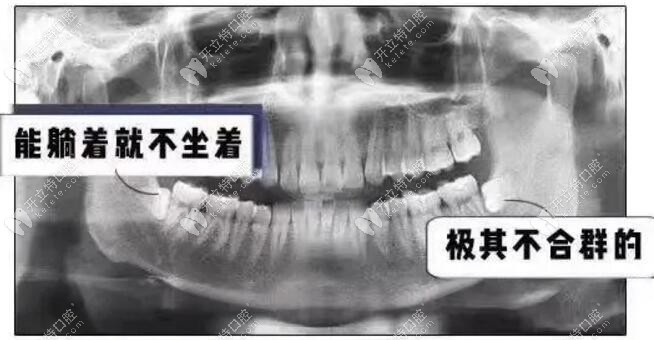

▼智齒空間不足的圖片-需盡快拔除▼

智齒空間不足的圖片-需盡快拔除